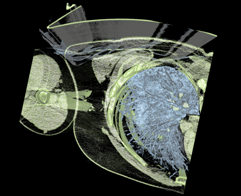

- Broken arm, 512x512x102, 2D transfer, raycasting

- Broken arm, 512x512x102, 2D transfer, raycasting, clipping plane